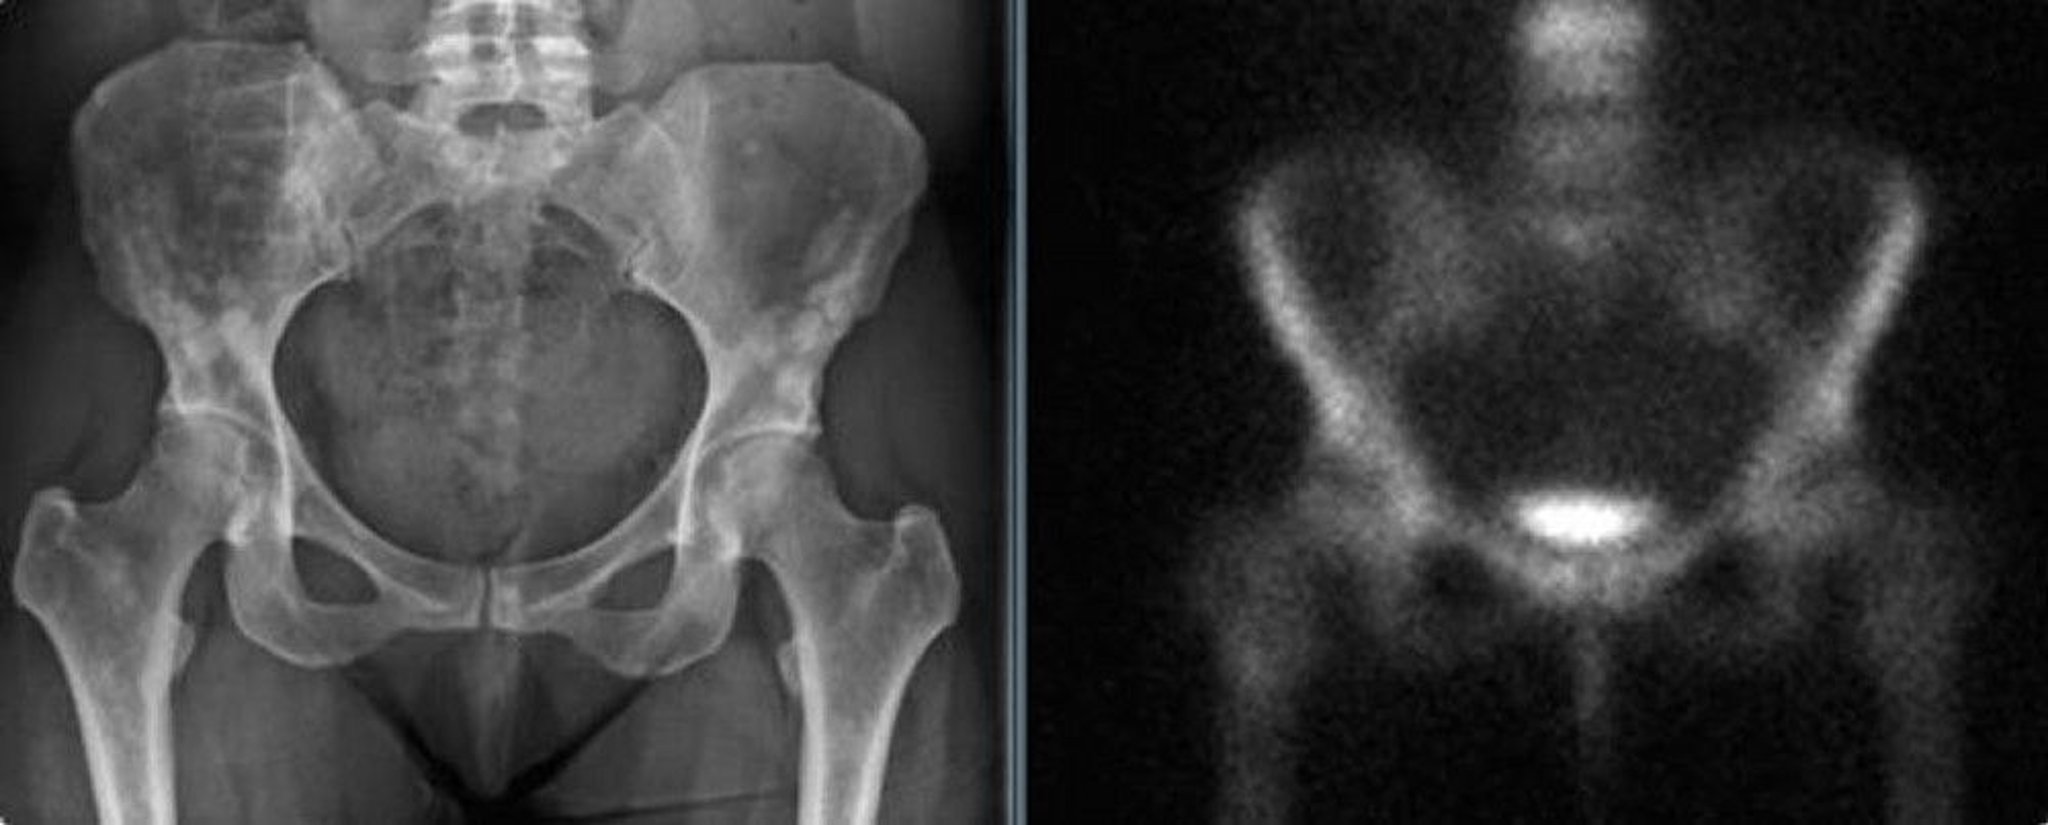

55歳女性の骨盤に生じた骨斑紋症のX線写真(転倒の可能性があった後に撮影)であり,陰影が乳房の造骨性転移と間違えられる可能性がある(左)。骨シンチグラフィーでは有意な集積亢進を認めない(右)。

Images courtesy of Michael J.Joyce, MD, and David M.Joyce, MD.